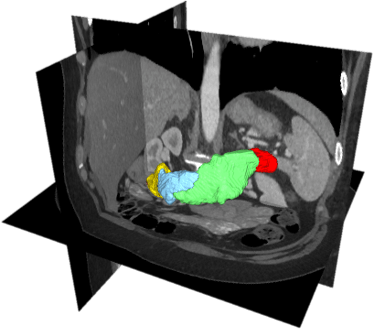

Pancreatic cancer surgery

Pancreatic cancer is currently the 4th and projected to be the 2nd leading cause of cancer-related death in developed countries. Pancreatic cancer is often detected on late stages and the percentage of unsuccessful/exploratory tumor removal attempts can vary from 24% to 63% for different hospitals in European countries. This project applies machine learning solution for improving pancreatic cancer treatment. The particular aims are to automatically segment pancreatic tumor, pancreas subparts, and abdominal vasculature, improve cancer visualization and access the surgery success attempts. The project will also evaluate the benefits of augmenting pancreatic cancer surgery with other treatment modalities.